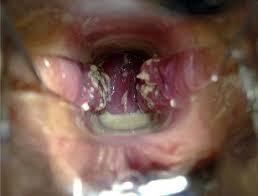

1. bucofaringea

1. Mucocutánea

2. Manifestación clinicas